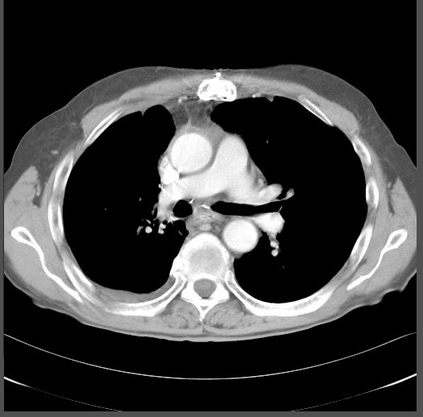

The evaluation of infectious disease processes on radiologic images is an important and challenging task in medical image analysis. Pulmonary infections can often be best imaged and evaluated through computed tomography (CT) scans, which are often not available in low-resource environments and difficult to obtain for critically ill patients. On the other hand, X-ray, a different type of imaging procedure, is inexpensive, often available at the bedside and more widely available, but offers a simpler, two dimensional image. We show that by relying on a model that learns to generate CT images from X-rays synthetically, we can improve the automatic disease classification accuracy and provide clinicians with a different look at the pulmonary disease process. Specifically, we investigate Tuberculosis (TB), a deadly bacterial infectious disease that predominantly affects the lungs, but also other organ systems. We show that relying on synthetically generated CT improves TB identification by 7.50% and distinguishes TB properties up to 12.16% better than the X-ray baseline.

翻译:放射图像中的传染病过程评估是医学图像分析中一项重要而具有挑战性的任务。 肺感染通常可以通过计算成的XX扫描进行最佳的成像和评估,这些扫描往往在资源贫乏的环境中得不到,而且病人很难获得。另一方面,X光是一种不同类型的成像程序,价格低廉,常常在床边提供,而且可以更广泛地获得,但提供一种更简单、更简单的二维图像。我们表明,通过依靠一种能够学会合成X光生成CT图像的模式,我们可以提高自动疾病分类的准确性,并向临床医生提供对肺病过程的不同看法。具体地说,我们调查结核病,这是一种致命的细菌传染病,主要影响肺部,但也影响其他器官系统。我们表明,依靠人工生成的CT,可以提高7.50%的结核病识别率,并将结核病特性区分为12.16%,比X光基线要好得多。